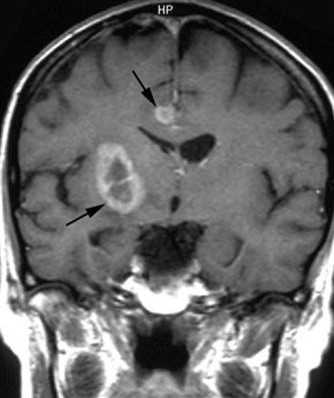

МРТ головного мозга. Туберозный склероз. Гигантоклеточная внутрижелудочковая астроцитома (стрелки). Прорастание в хвостатое ядро. Окклюзия отверстия Монро. Т2-зависимая, Т1-зависимая и Т1-зависимая с контрастированием аксиальные МРТ.

При МРТ доброкачественные астроцитомы чаще выглядят однородными, хотя возможна неоднородность в связи с кальцинатами (до 20% случаев) и микрокистозной дегенерацией. Границы опухоли четкие. Вазогенный отек выражен только при низкодифференцированном подтипе. Астроцитома может вовлекать кору мозга и напоминать острый ишемический инсульт. Различать их при МРТ помогает отчетливо клиновидная форма при инсульте, совпадающая с бассейном кровоснабжения. Нередко при МРТ головного мозга встречаются “кистозные” астроцитомы, когда сама опухоль имеет небольшие размеры, а прилежащая ликворная киста значительно больше ее самой. Анапластические астроцитомы на МРТ хорошо усиливаются при контрастировании, доброкачественные астроцитомы усиливаются при МРТ с контрастированием примерно в 40% случаев. Изредка встречаются первично-множественные астроцитомы. Гигантоклеточная внутрижелудочковая астроцитома встречается только при туберозном склерозе. При МРТ она имеет типичное расположение и хорошо контрастируется.

Субэпендимальные, то есть проецирующиеся в желудочек, но растущие со стороны паренхимы мозга, узлы чаще расположены рядом с хвостатым ядром или гипоталамической бороздой сразу за отверстием Монро, реже в области III, IV желудочков и Сильвиева водопровода. На Т2-взвешенных томограммах субэпендимальные узлы умеренно гиперинтенсивны и часто содержат кальцинаты . От астроцитом их отличает не столь яркий сигнал и меньшие размеры. Контрастирование при введении препаратов гадолиния иногда наблюдается и в субэпендимальных узлах , и всегда в астроцитомах.